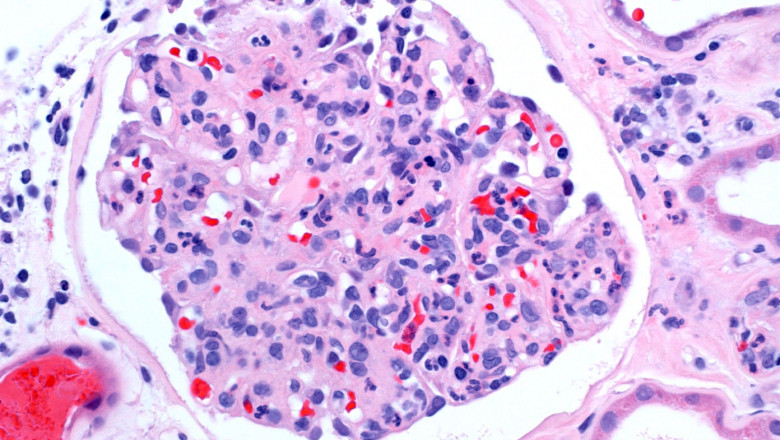

Eosinophilic esophagitis can be diagnosed using radiography, endoscopy,esophagogastroduodenoscopy biopsy. Effectiveness and the choice of treatment for eosinophilic esophagitis depend on the family's decision to address both the disease's origin and symptoms while sacrificing some aspects of life quality.Eosinophilic Esophagitis (EoE) is a persistent esophageal immune system condition. The inner lining of the oesophagus in EoE has an abundance of white blood cells called eosinophils. The oesophagus tissue may become inflamed or harmed as a result of this buildup, which is a reaction to food, an allergy, or acid reflux. Adults with eosinophilic esophagitis experience difficulties swallowing, impaction, chest pain that is frequently centred and does not improve with antacids, and the backflow of undigested food.

Eosinophilic esophagitis disorder can be brought on by things like esophageal injury, eosinophil growth, and esophageal response. Although the actual source of the condition is unknown, allergic immunological reactions to specific foods or environmental proteins may produce and accumulate a significant number of eosinophils in one area. Other contributing factors include radiation therapy, some antibiotic medicines, and acid reflux. Children and adults have been known to have the illness, which is more common in men than women. Eosinophilic Esophagitis is more common in those who live in cold or dry climates, have a family history of the condition, have other allergies, or have asthma. The most typical signs of eosinophilic esophagitis include nausea, vomiting, chest pain, dysphagia, and food being stuck in the throat (impaction).